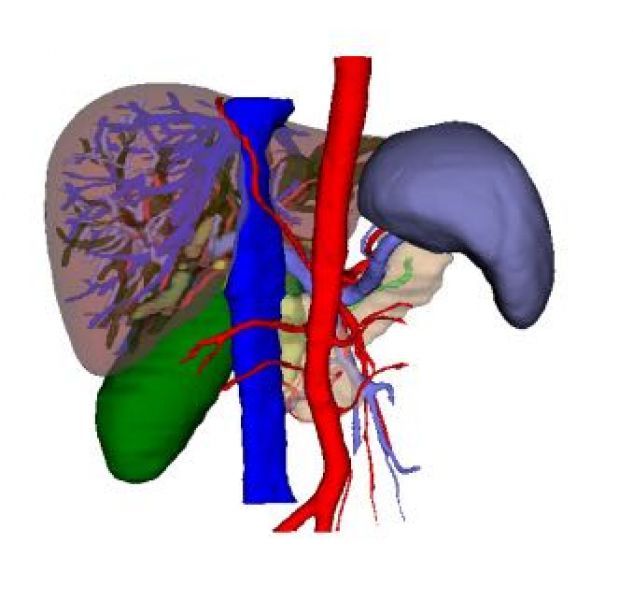

考虑到肝内错综复杂的解剖结构,明确病变肝脏与邻近重要管道组织的关系,医生们再次和患方沟通并取得理解和支持,利用最新的计算机多维数字图像处理技术以及多维测量技术和专业网络技术对其CT图像进行3D可视化处理,提供了数字化三维模型,医生们更清晰的了解病变器官及周围器官的立体组织结构和管道变异情况,制定了更为精准的手术方案。同时,为了避免手术过程中的医源性损伤,医生们为患者进行了术前模拟手术,决定逆向思维,优势右手为主操作,从穿刺孔的布局,术者的站位,助手的配合,麻醉师的操作...具体每一个操作细节均在模拟器上进行了模拟,并取得了理想的效果,坚定了术者的信心。

“镜面人”的成因是胚胎发育过程中的正常变异,是心、肺、胃、肝、脾、肠等内脏转位 180°,全部长反了位置,就像正常人在镜子中的影像一样,其概率约为百万分之一,在医学界较为罕见。正常人胆管炎发作表现为右上腹疼痛,放散至后背,“镜面人”患者却表现为左上腹部疼痛,同样向后背放散,该患者在州医院完成了影像学等检查,确认为一例典型的“镜面人”。通常行腹腔镜手术时,主刀医师和助手已形成固定的操作习惯和模式,而镜面像患者需反向搭配,手术顺序步骤和正常一样,习惯的改变有造成术中误伤周边脏器的可能,导致不良后果。针对“镜面人”的腹腔镜下解剖性肝切除手术,目前国内外文献鲜有报道,该手术得以顺利完成,得益于精确的术前设计,术前3D可视化有助于精确判断肝内重要的解剖标志,医生们针对术前资料细致的研究,熟悉了“镜面人”的肝内脉管的走行,精准把控切肝范围。遵循人体工程学原理,不断“反向思维”,针对术中具体操作难点进行术前模拟操作,并突破技术瓶颈,找到解决方案。术后医护合作,不断思考,为患者实施有效的加速康复管理措施,为类似罕见病例积累了宝贵的诊疗经验。

术前3D可视化(前面观,后面观)